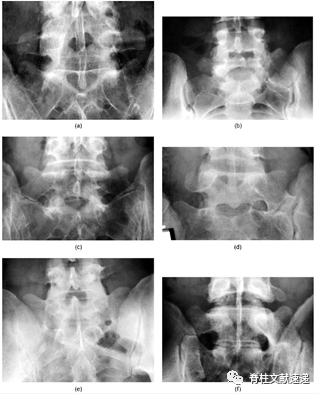

1984年,Castellvi等基于腰骶移行椎的形态学特征将其分为4型(如图1所示):

I型:主要为腰5横突发育不良,横突宽度至少大于19mm,并将其分为两个亚型Ia(单侧横突发育不良)或Ib(双侧横突发育不良)。

II型:表现为不完全的腰椎骶化,具有增宽的横突,并且和骶骨之间存在联系形成关节,并将其分为两个亚型IIa(单侧关节形成)或IIb(双侧关节形成)。

III型:单侧(IIIa)或双侧(IIIb)腰椎完全骶化,腰5横突与骶骨完全骨性融合。

IV型:一侧为II型即腰5横突与骶骨之间存在联系形成关节,对侧为III型即腰5横突与骶骨完全骨性融合。

图1

1、X线:腰骶移行椎的典型鉴定方法就是通过侧位和弗格森位X线片(即X线球管向头侧倾斜30°,可更好的显示腰5横突及其与骶骨的关系)来鉴定。

图2注:(a)Ib型LSTV,L5双侧横突增宽,但与骶骨未形成关节;(b)IIa型LSTV,L5单侧横突增宽,单侧假关节形成;(c)IIb型LSTV,L5双侧横突增宽,双侧假关节形成;(d)IIIa型LSTV,L5单侧横突增宽,并与骶骨形成骨性融合;(e)IIIb型LSTV,L5双侧横突增宽,并与骶骨形成骨性融合;(f)IV型LSTV,左侧形成骨性融合,右侧形成假关节。